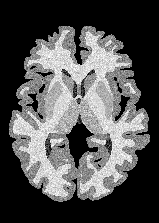

4.2 Registration to a 100 micron ex-vivo brain MRI volume

To showcase the efficacy of our method on real large scale images, we register a 250 in-vivo MRI image (Lüsebrink et al., 2017) to a 100 ex-vivo FLASH human brain volume (Edlow et al., 2019). This represents an inverse problem with more than 11.2B optimizable parameters (compared to 20M for clinical datasets), or 44.8GB of GPU memory. The entire problem does not fit on most GPUs, necessitating distributed multimodal registration. We optimize a composite transform - affine followed by a diffeomorphic mapping; details can be found in Section E.1. Multimodal deformable registration took 58 seconds on 8 NVIDIA A6000 GPUs, which is unprecedented at this resolution. Fig. 6 shows qualitative results, highlighting the ability to register highly detailed structures such as cerebellar white matter; these structures are not visible at macroscopic scales. The resultant advantages of performing registration at this scale can allow researchers to characterize the neuroanatomy at microscopic resolutions and allow morphometric analysis of cortical layers and subcortical nuclei among other structures.